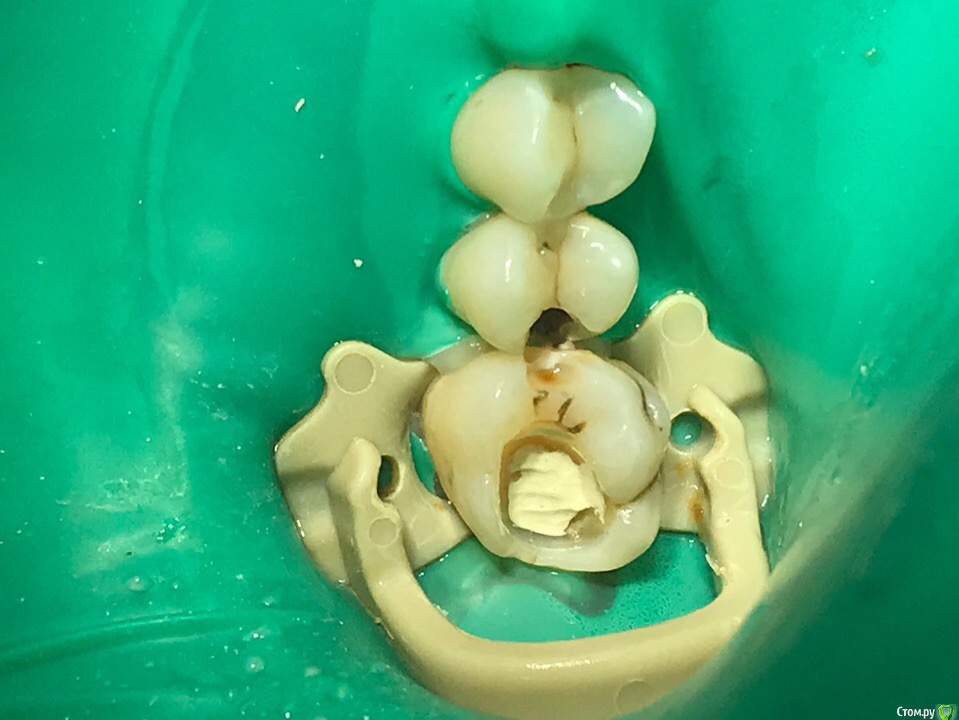

1586Doc Опубликовано 7 июня, 2019 Автор Поделиться Опубликовано 7 июня, 2019 все в кучу ) Ссылка на комментарий